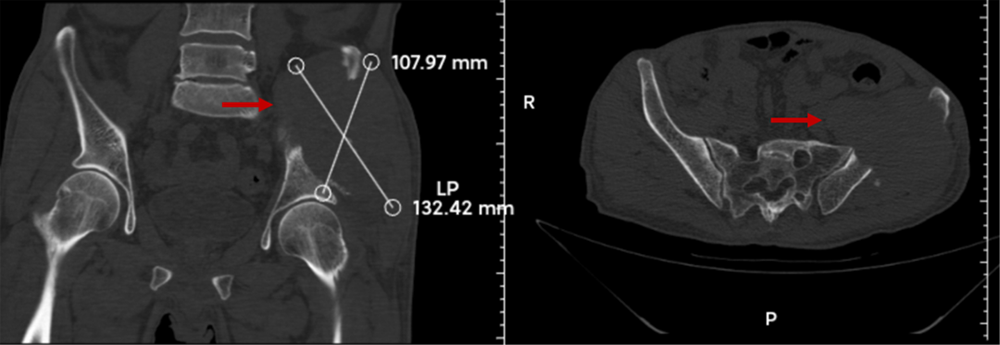

患者李先生(化名)因左侧髋骨剧烈疼痛入院。据其自述,疼痛剧烈致无法平卧及行走,甚至咳嗽时亦引发剧痛,日常生活受到严重影响。经骨病与骨肿瘤科苏情医生团队详细问诊及查体发现,患者两年前曾确诊右侧肾癌但未接受治疗。一周前突发左侧髋部剧痛,影像学检查提示左侧髂骨存在明显骨质破坏,并见一巨大软组织肿块突入盆腔。入院后患者呈严重贫血状态,凝血机制明显异常。穿刺活检病理结果证实,该肿瘤为肾癌骨盆转移。

该患者的左侧髂骨存在明显骨质破坏,巨大软组织肿块突入盆腔。

骨盆恶性肿瘤因其发现晚、肿瘤体积大、术中出血风险高及局部解剖结构复杂等因素,手术难度与风险极大。传统治疗方式多采用半骨盆截肢术,但会给患者带来巨大的心理创伤。保肢手术虽能改善患者生活质量,但对手术技术要求极高。尤其该患者因原发肾癌影响,同时伴有严重贫血与凝血功能障碍,进一步增加了手术风险与挑战。